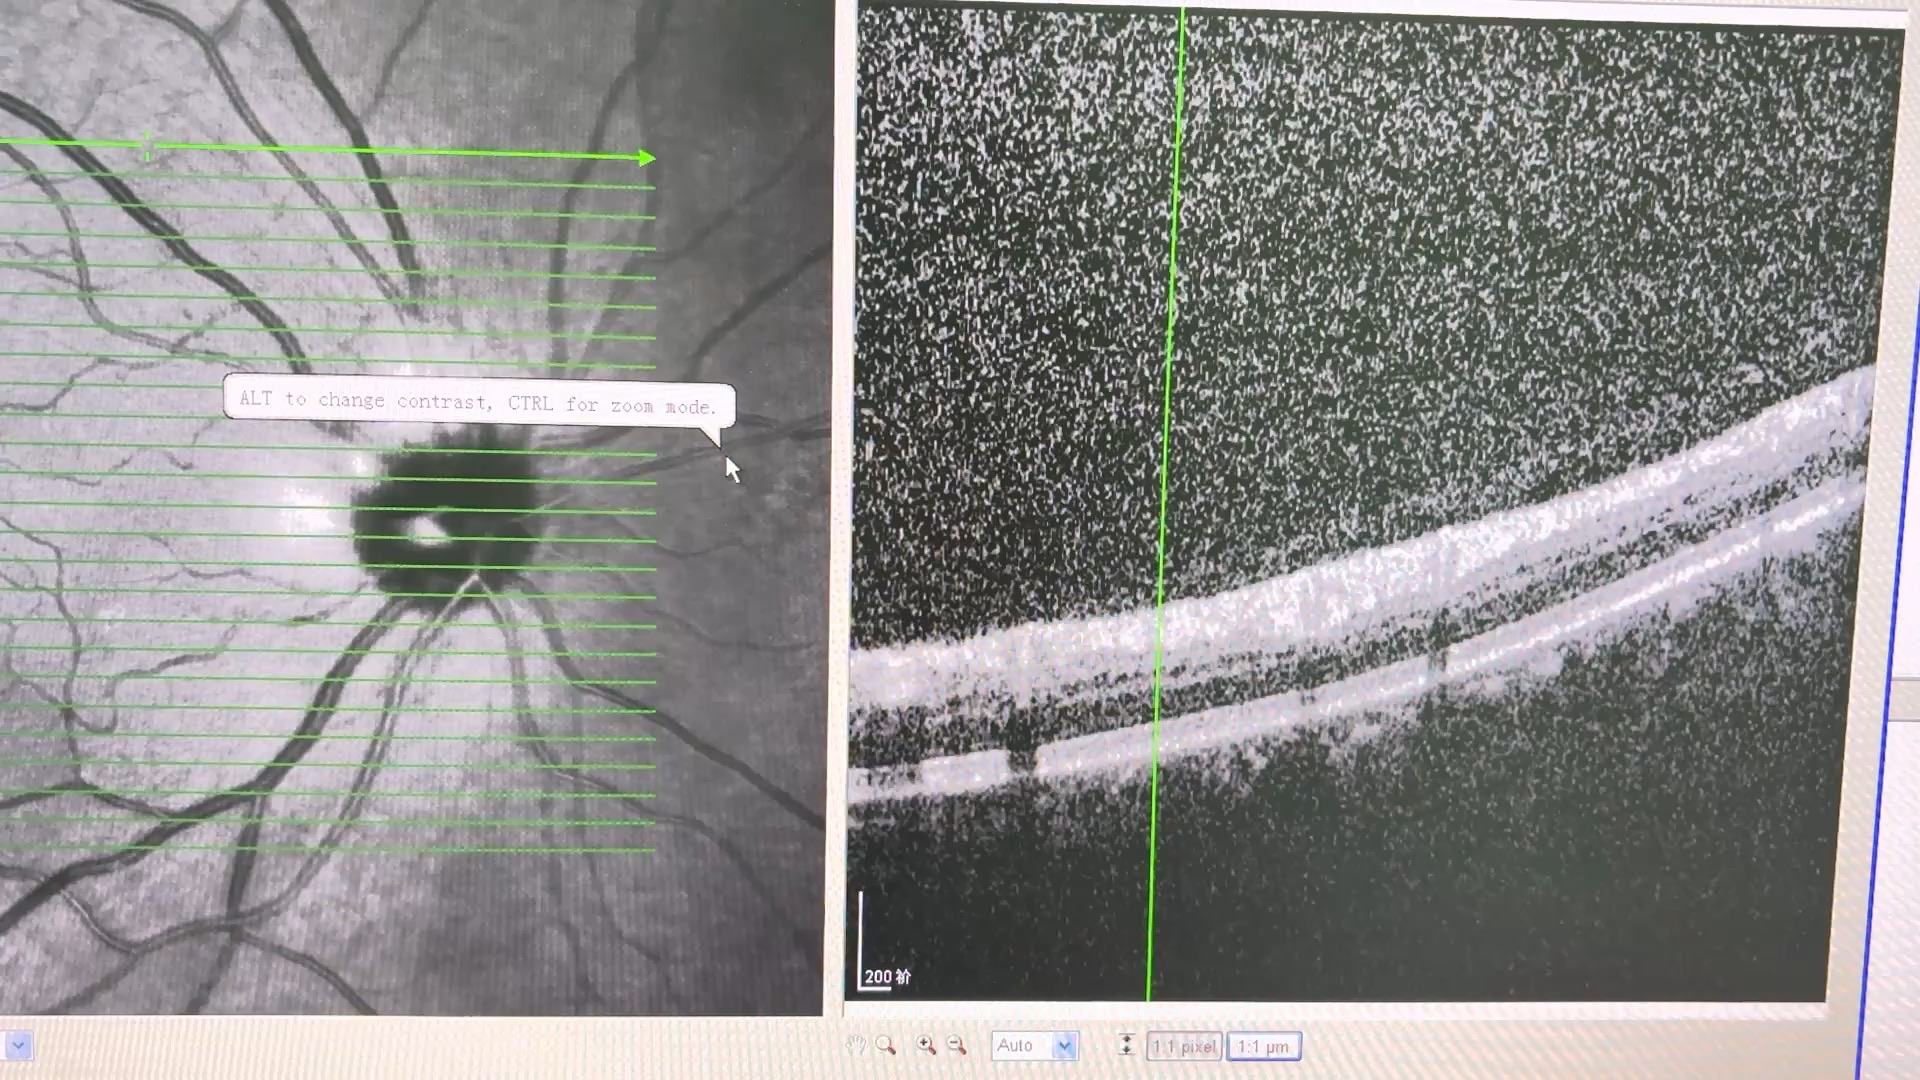

61岁糖尿病患者眼底筛查,视力双眼0.8,晶体皮质轻混浊,眼底见右眼上方,左眼下方圆形病灶。

视盘旁长ODD吗?